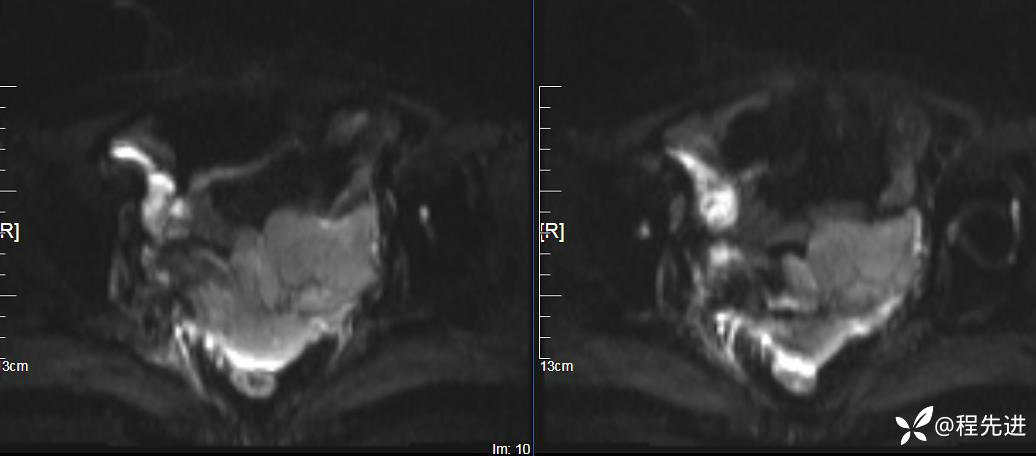

T2压脂: